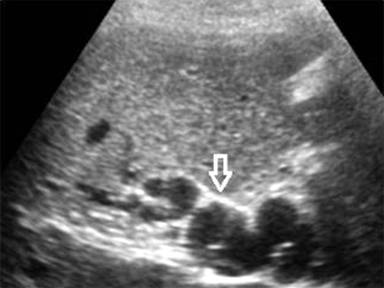

When the thrombus occludes the main PV, the hepatopetal flow is maintained via cavernous transformation of the portal vein (CTPV) (Figure 1) [14]. Besides, a lumen occluding thrombus, a pseudocyst or mass-forming chronic pancreatitis may also cause extrinsic compressions on veins and consequently CTPV [4]. CTPV comprises of two system of veins: the paracholedochal veins of Petren, that run parallel to biliary duct wall and the epicholedochal veins of Saint, that are located on the surface of bile ducts [15]. It takes approximately 3 weeks’ time for cavernous transformation to occur [16]. CTPV is found in 70 -100% of patients suffering from PV thrombosis. In spite of numerous collateral pathways, portal hypertension (PH) still occurs. Patients become symptomatic on account of features of portal hypertension i.e., bleeding from collaterals and splenomegaly than due to biliary obstruction caused by enlarged collaterals [16]. Variceal haemorrhage at presentation however, does not influence overall survival [17].

|

Figure 1. Sonogram shows replacement of main portal vein with multiple serpiginous, anechoic channels (arrow) that on color Doppler interrogation revealed slow flow. |

Ultrasonography is the initial investigation that reveals numerous anechoic vascular channels at porta. Gold standard for diagnosis of CTPV is conventional angiography. However, MR angiography is as accurate as conventional angiography. A prophylactic surgery in this case is debatable with some surgeons intervening only on development variceal hemorrhage. Endoscopic management in the form of band ligation or sclerotherapy are preferred procedures. Portosystemic shunt is created in those who fail to benefit from endoscopic measures. [17] PV thrombosis with CTPV limits the success of TIPS since accessibility of PV via transjugular route becomes difficult in chronically thrombosed vein [18]. Moreover, passage of wire through one of the collaterals across the occluded segment is either difficult or impossible. Hence, PV thrombosis with CTPV, a contraindication to TIPS [18]. However, Jourabchi described a case of CP associated CTPV where TIPS was performed employing a combined transjugular and transhepatic approach [18].